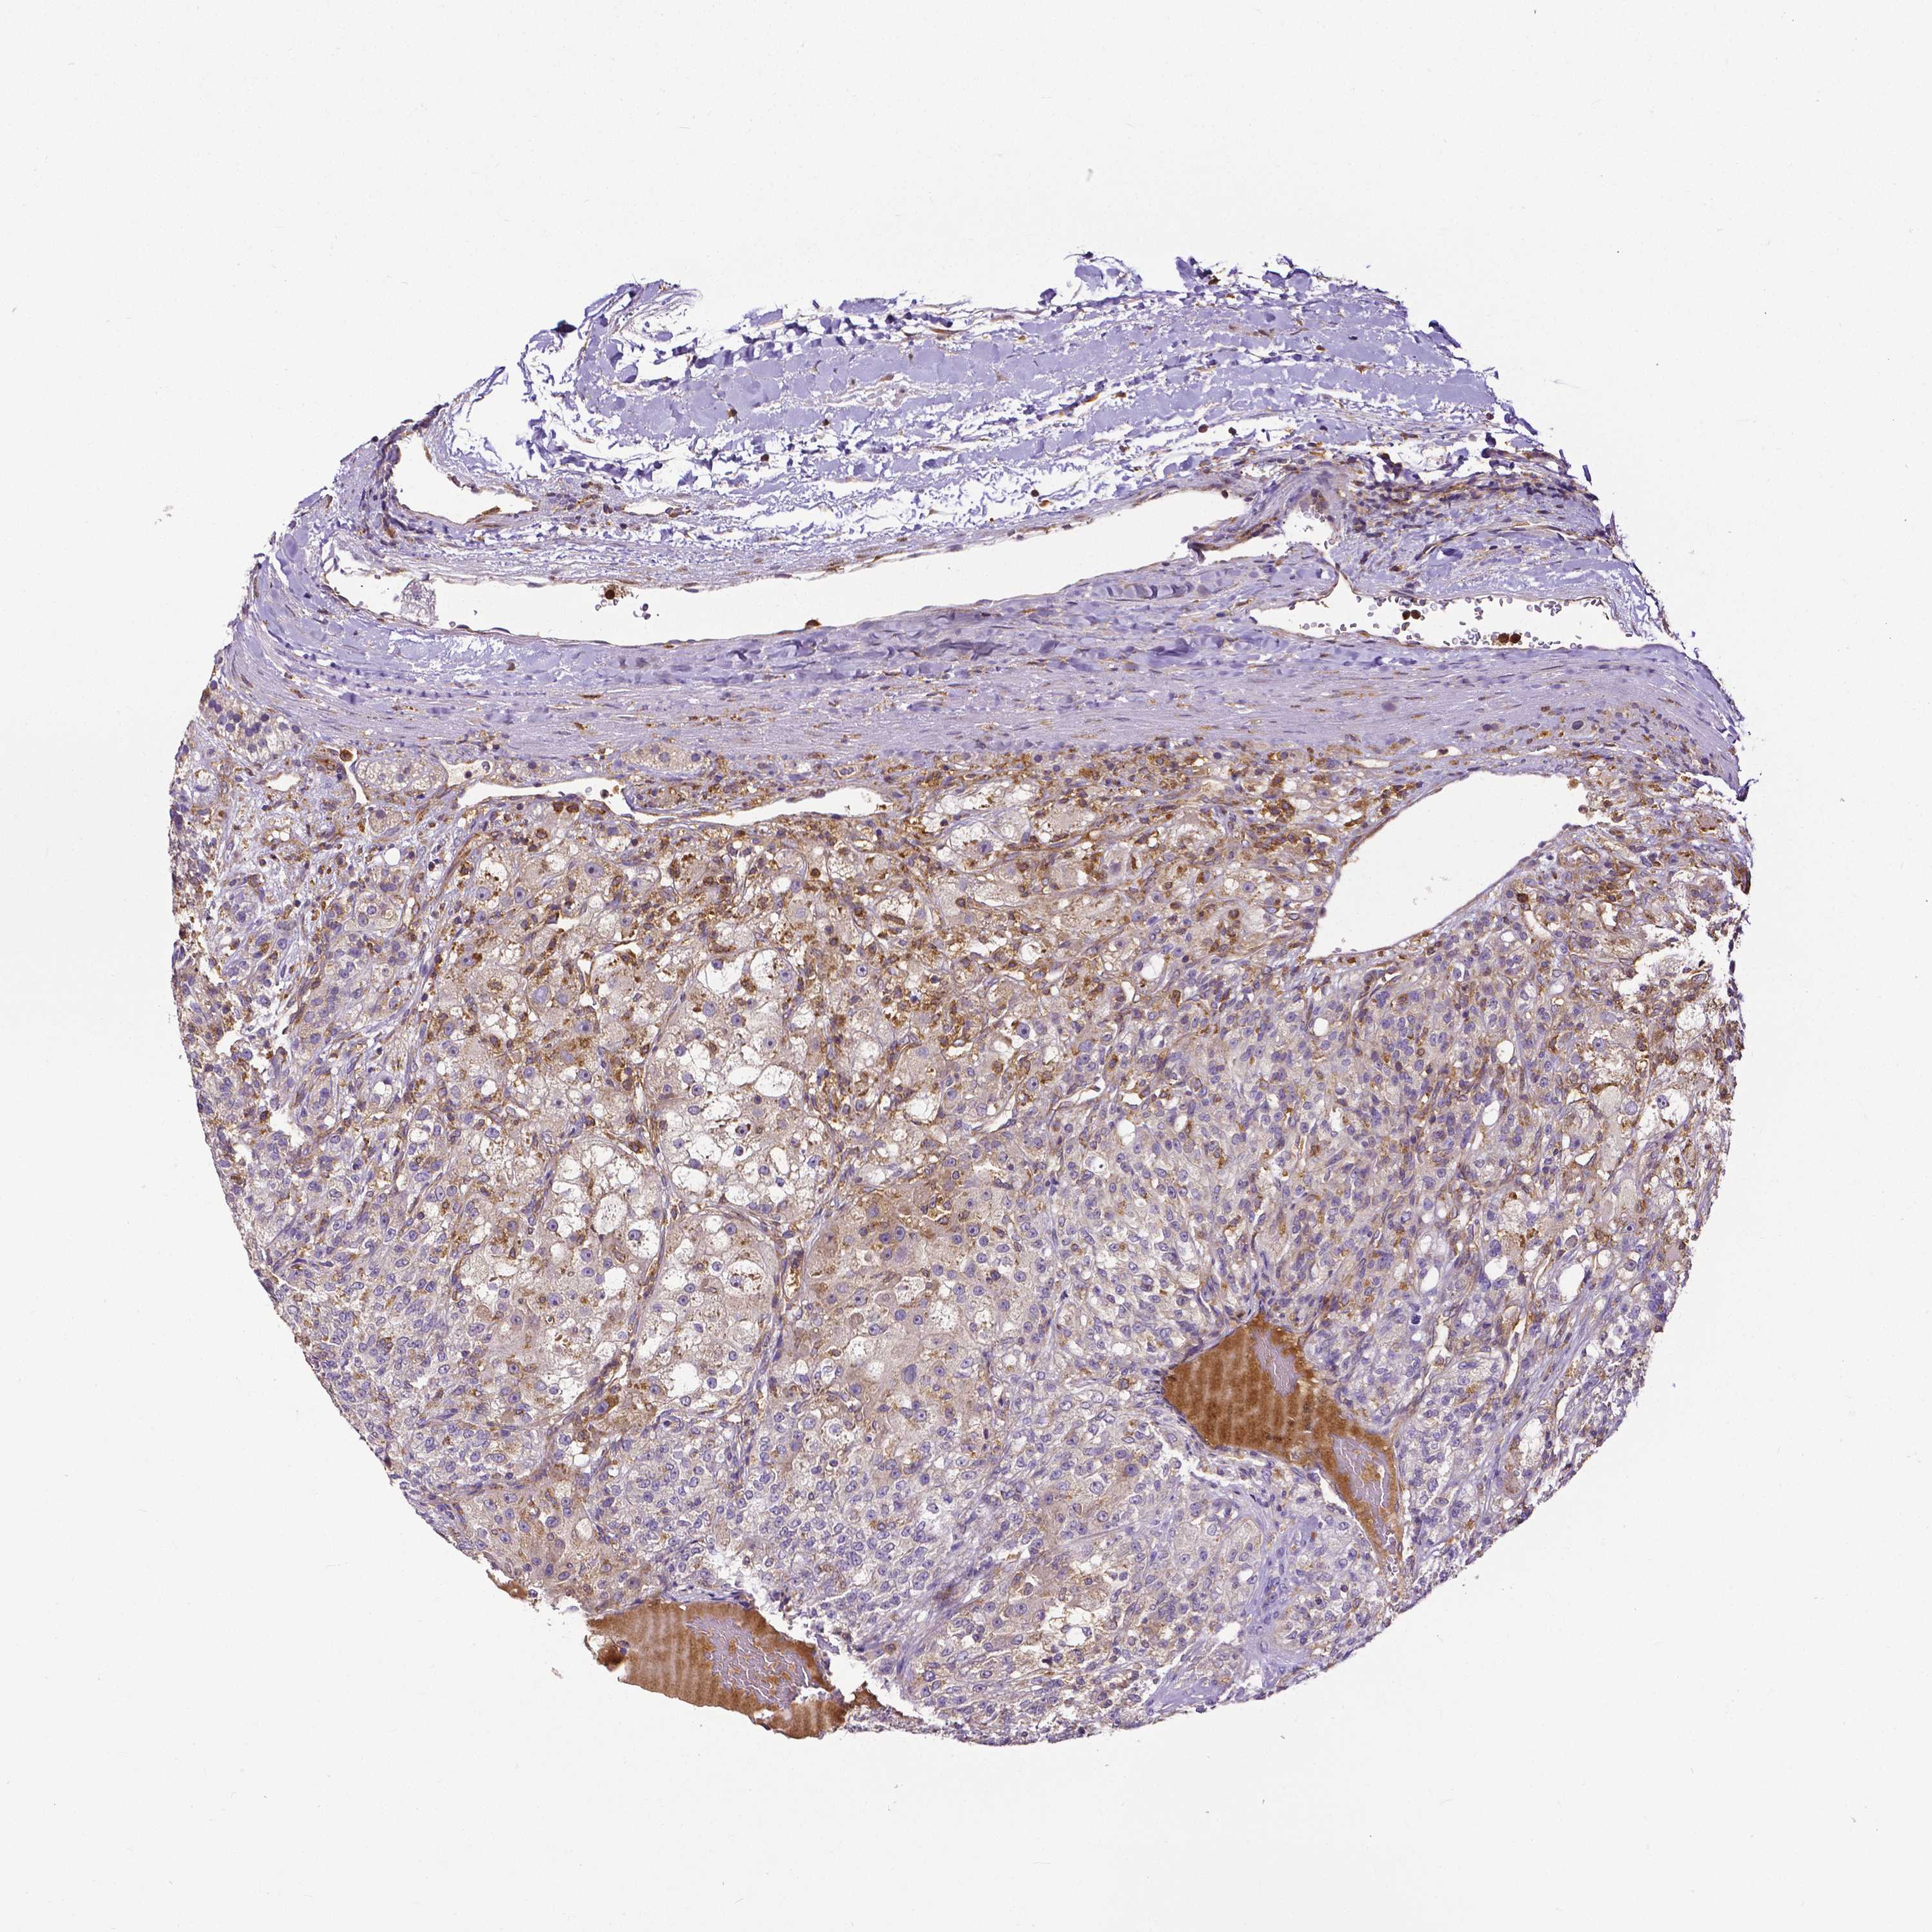

KIDNEY RENAL CLEAR CELL CARCINOMA (TCGA) - Interactive survival scatter ploti

The Survival Scatter plot shows the clinical status (i.e. dead or alive) for all individuals in the patient cohort, based on the same data that underlies the corresponding Kaplan-Meier plots. Patients that are alive at last time for follow-up are shown in blue and patients who have died during the study are shown in red.

The x-axis shows the expression levels (FPKM) of the investigated gene in the tumor tissue at the time of diagnosis. The y-axis shows the follow-up time after diagnosis (years). Both axes are complimented with kernel density curves demonstrating the data density over the axes. The top density plot shows the expression levels (FPKM) distribution among dead (red) and alive patients (blue). The right density plot shows the data density of the survived years of dead patients with high and low expression levels respectively, stratified using the cutoff indicated by the vertical dashed line through the Survival Scatter plot. This cutoff is automatically defined based on the FPKM cutoff that minimizes the p-score. The cutoff can be changed by dragging the vertical line or by entering a cutoff value in the square labeled "Current cut-off".

Under the Survival Scatter plot the p-score landscape (black curve; left axis) is shown together with dead median separation (red curve; right axis). Dead median separation is the difference in median mRNA expression between patients who have died with high and low expression, respectively. It is calculated as follows: median FPKM expression of dead patients with high expression - median FPKM expression of dead patients with low expression. This is intended to aid the user in visually exploring custom cutoffs and the associated p-scores and dead median separation.

Individual patient data is displayed and can be filtered by clicking on one or more of the category buttons on the top of the page. Categories describing expression level and patient information include: high, low, alive, dead, female, male and tumor stages. The scale of the x-axis can be toggled between linear and log-scale by clicking on the "x log" button. Mouse-over function shows TCGA ID, patient information and mRNA expression (FPKM) for each patient.

& Survival analysisi

Kaplan-Meier plots summarize results from analysis of correlation between mRNA expression level and patient survival. Patients were divided based on level of expression into one of the two groups "low" (under cut off) or "high" (over cut off). X-axis shows time for survival (years) and y-axis shows the probability of survival, where 1.0 corresponds to 100 percent.

DICER1 is potential prognostic, high expression is favorable in Kidney Renal Clear Cell Carcinoma (TCGA)

Best expression cut offi

Based on the FPKM value of each gene, patients were classified into two groups and association between prognosis (survival) and gene expression (FPKM) was examined. The best expression cut-off refers the FPKM value that yields maximal difference with regard to survival between the two groups at the lowest log-rank P-value. Best expression cut-off was selected based on survival analysis .

When clicking on this number, the vertical dashed line indicating cut-off, the interactive survival plot, and the Kaplan-Meier curve will be adjusted to show results based on the best expression cut-off.

: 3.99

TCGA RNA samplesi

RNA-seq data is reported as average FPKM (number Fragments Per Kilobase of exon per Million reads), generated by the The Cancer Genome Atlas (TCGA) .

Normal distribution across the dataset is visualized with box plots, shown as median and 25th and 75th percentiles. Points are displayed as outliers if they are above or below 1.5 times the interquartile range. FPKM values of the individual samples are presented next to the box plot.

Average pTPM 4.9

Number of samples 521